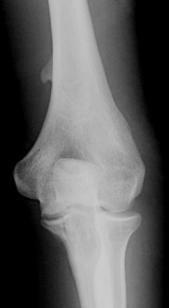

What is the abnormality and what symptoms are usually associated?

Supracondylar Process

Associated with Pronator Syndrome